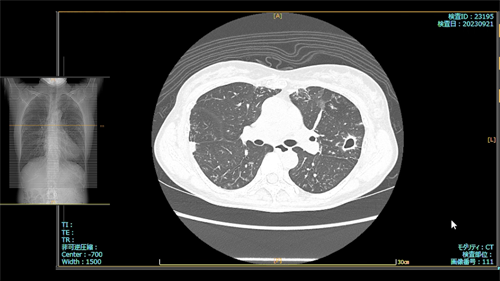

肺X線画像

- 2023.09.21 入院加療の必要ありと診断された画像(国立系病院)